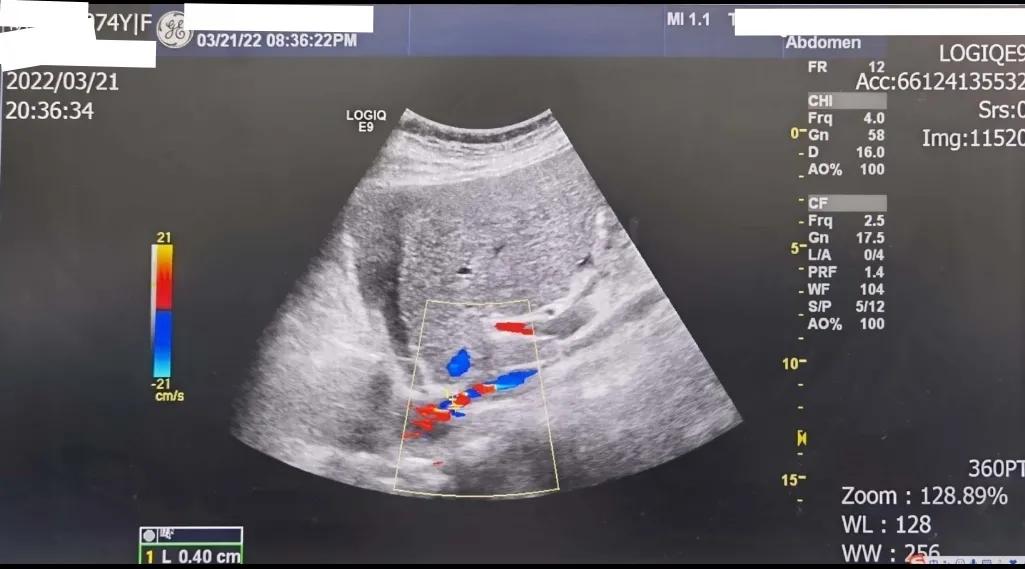

于是,马上联系B超室,安排患者进行下腔静脉B超检查,结果提示:下腔静脉内径约4-12mm,入右心房处管径细约4mm,流速增快,最快达184cm/s,高度提示布加综合征不能除外,建议进一步检查。假如进一步检查明确,或球囊扩张或支架植入,治疗效果不言而喻。

腹部B超检查发现,下腔静脉入右房处管径明显变细,管腔测量仅4mm